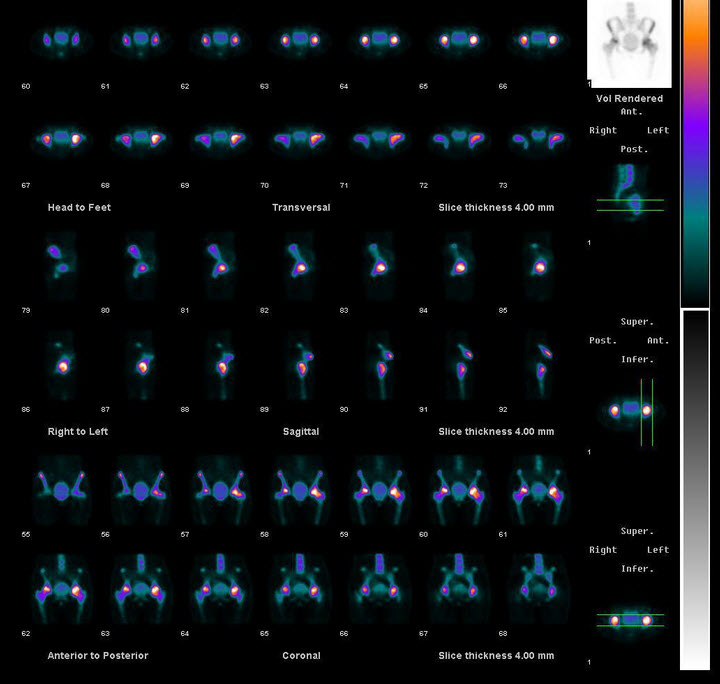

55、多项选择题

男性,65岁,急性心前区疼痛2天入院。行静息Tc-MIBI心肌显像如图,可能的诊断是()

A.下后壁心肌梗死

B.心尖心肌梗死